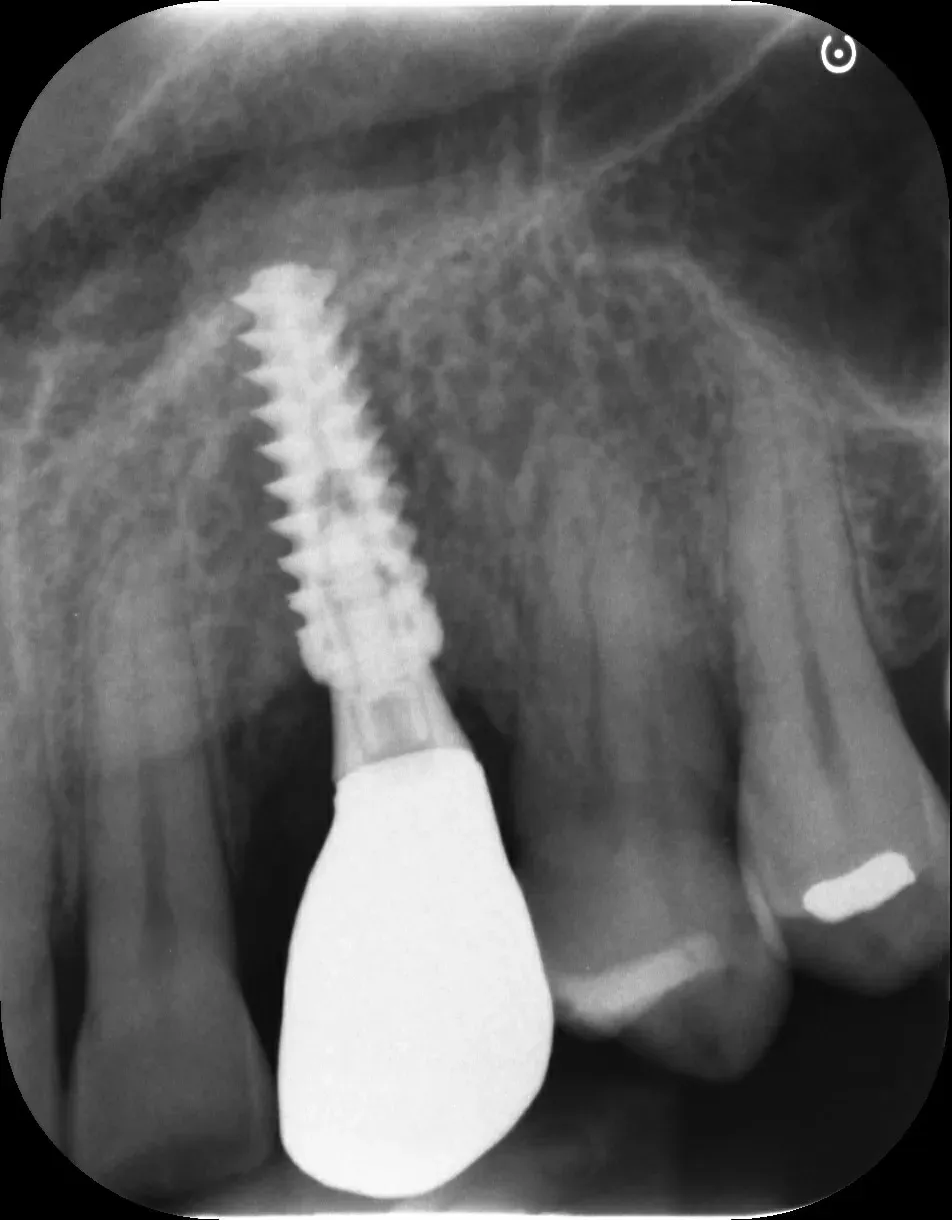

Gli impianti transmucosi devono essere posizionati transmucosi, soprattutto se hanno connessioni non particolarmente “sigillanti”. Usati in tal guisa, sono perfetti. Le immagini che seguono dimostrano che i transmucosi, se posizionati al giusto livello verticale, causano ZERO riassorbimento della cresta ossea.

Per concludere il confronto tra le varie connessioni, l’immagine che segue è una radiografia con due impianti affiancati: un tissue-level ben posizionato fatto da un collega anni addietro e un impianto a connessione conica in posizione infracrestale con abutment della corretta lunghezza per il caso. Il secondo è un mio caso. È interessante notare come il cono dello spazio biologico sia identico. Se ben posizionati, tutti gli impianti funzionano egregiamente (l’impianto più vecchio inizia a soffrire un pochino, ma questa è un’altra storia).